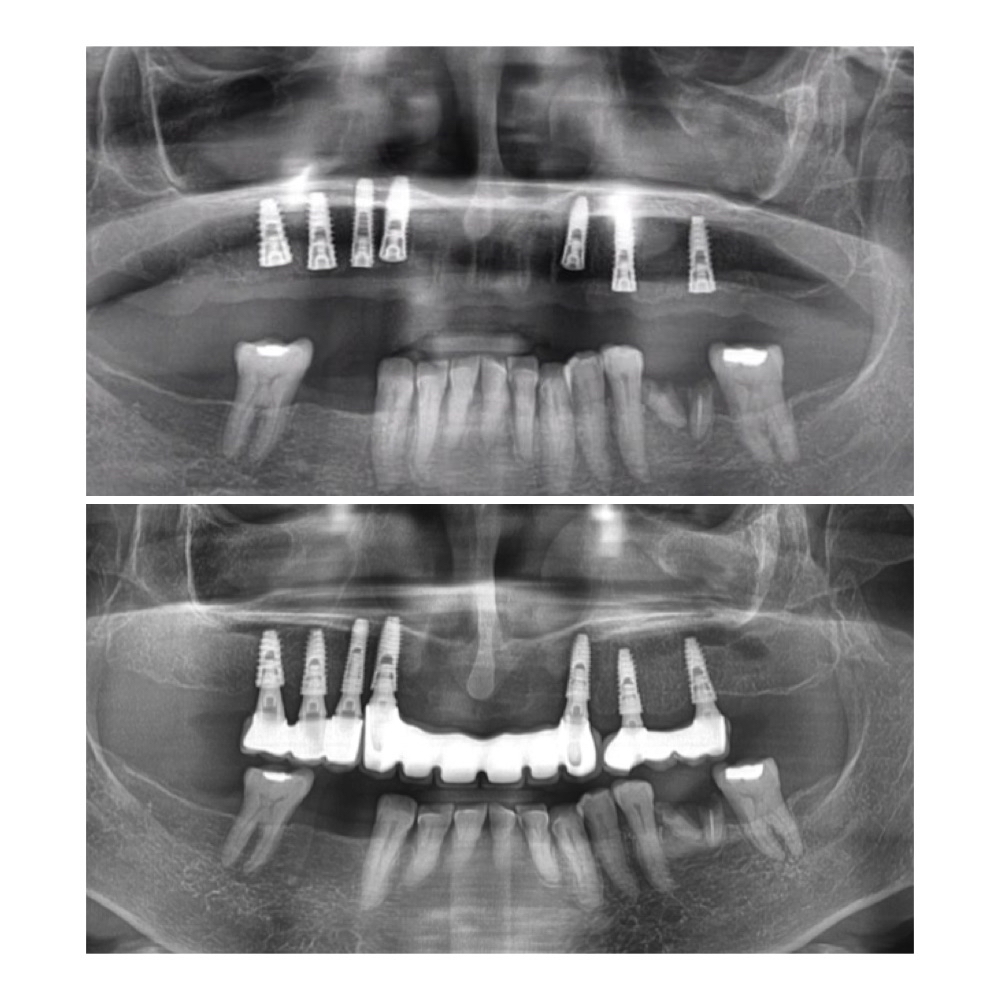

Titanium post placement, bone fusion, abutment, and crown attachment.

- Implant Placement: Surgically place a titanium post (implant) into the jawbone, serving as an artificial tooth root.

- Osseointegration: Allow bone fusion with the implant over several months for a strong bond.

- Abutment Attachment: Attach an abutment to the implant, protruding above the gumline for crown placement.

- Crown Placement: Secure a custom-made dental crown to the abutment, mimicking a natural tooth.